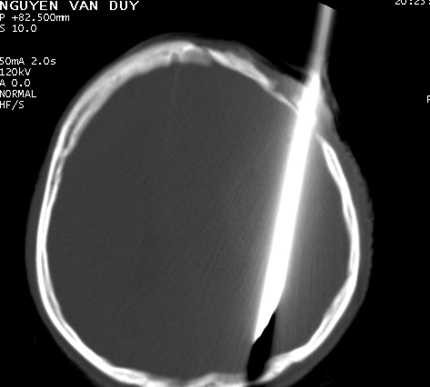

Trước đó, vào ngày 12/5, khoa cấp cứu bệnh viện này tiếp nhận bệnh nhân Duy trong tình trạng đầu bị một con dao lê (dài hơn 20cm, bản rộng 0,3cm đã bị gãy cán) đâm từ trán, xuyên não và xuyên ra vùng chẩm phía sau gáy.

Con dao đâm xuyên đầu nạn nhân.